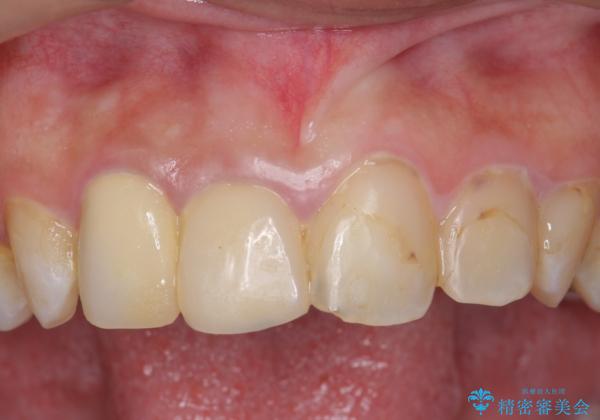

- 63.8万円(右上4~左上2:emaxクラウン 7万円x6本、仮歯 1万円x6本、歯周外科手術 15万円、右上1:精密根管再治療 9万円およびファイバーコア2万円)費用は治療当時の料金となります

隣の歯もつぎはぎでプラスチックが劣化していたため、虫歯を取りセラミックでかぶせました。

保険治療の前歯の被せものの縁(マージン)が歯茎の中まで及んでいたため、歯周外科手術を行い、マージンが歯肉縁下深くならないように設定しました。